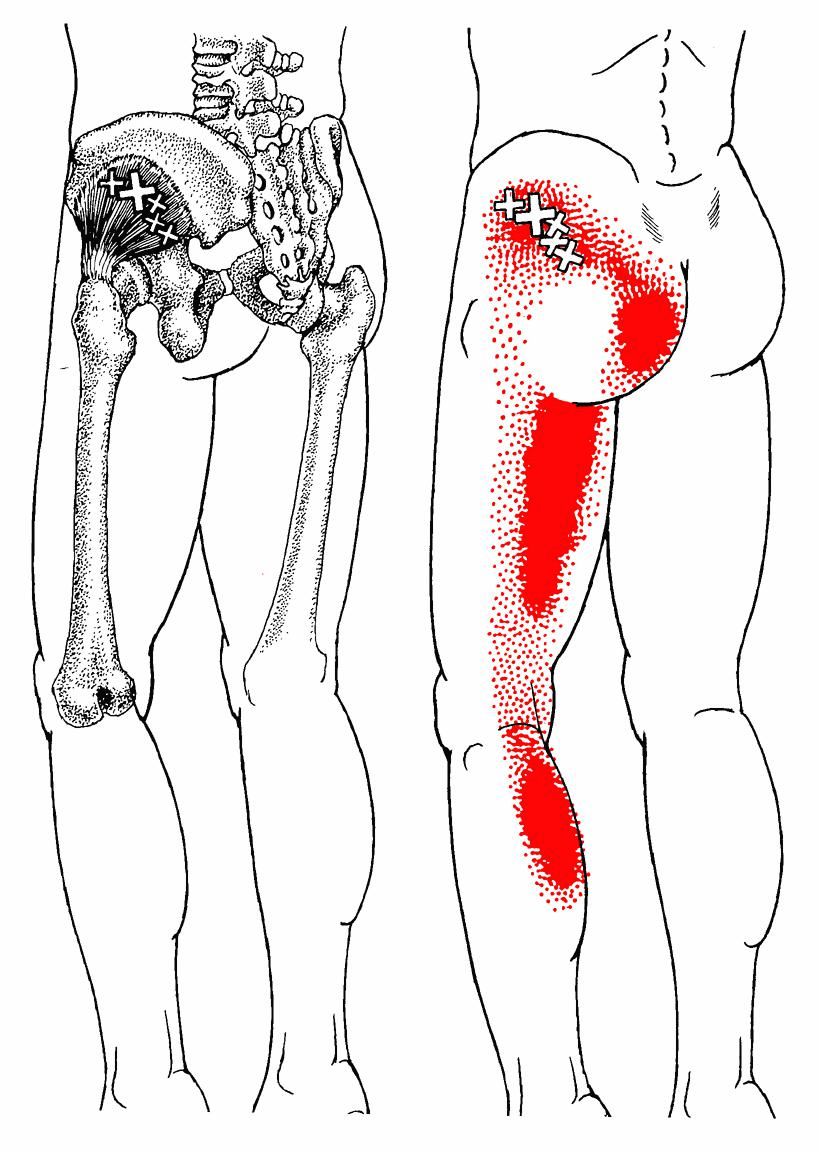

Piriformis Trigger Point Diagram 이상근의 TrPs의 경우 방사통은 천장관절부로 방사되기도 하며,

외측으로는 둔부 중앙을 넘어 고관절 후부와 대퇴 후부의 근위부 2/3로 방사됩니다.

넘어지려할 때 중심을 잡으려고 체중을 지탱하고 있는 다리를 급격히 내회전시킬 때(예를 들면, 달리기 하는 동안)와 같은 급성 과부하에서 초래됩니다.

차를 운전할 때 장시간 동안 대퇴를 외전 및 굴곡된 상태를 유지하는 것과 같은 지속적인 과부하는 이들 TrPs를 지속화시킵니다.